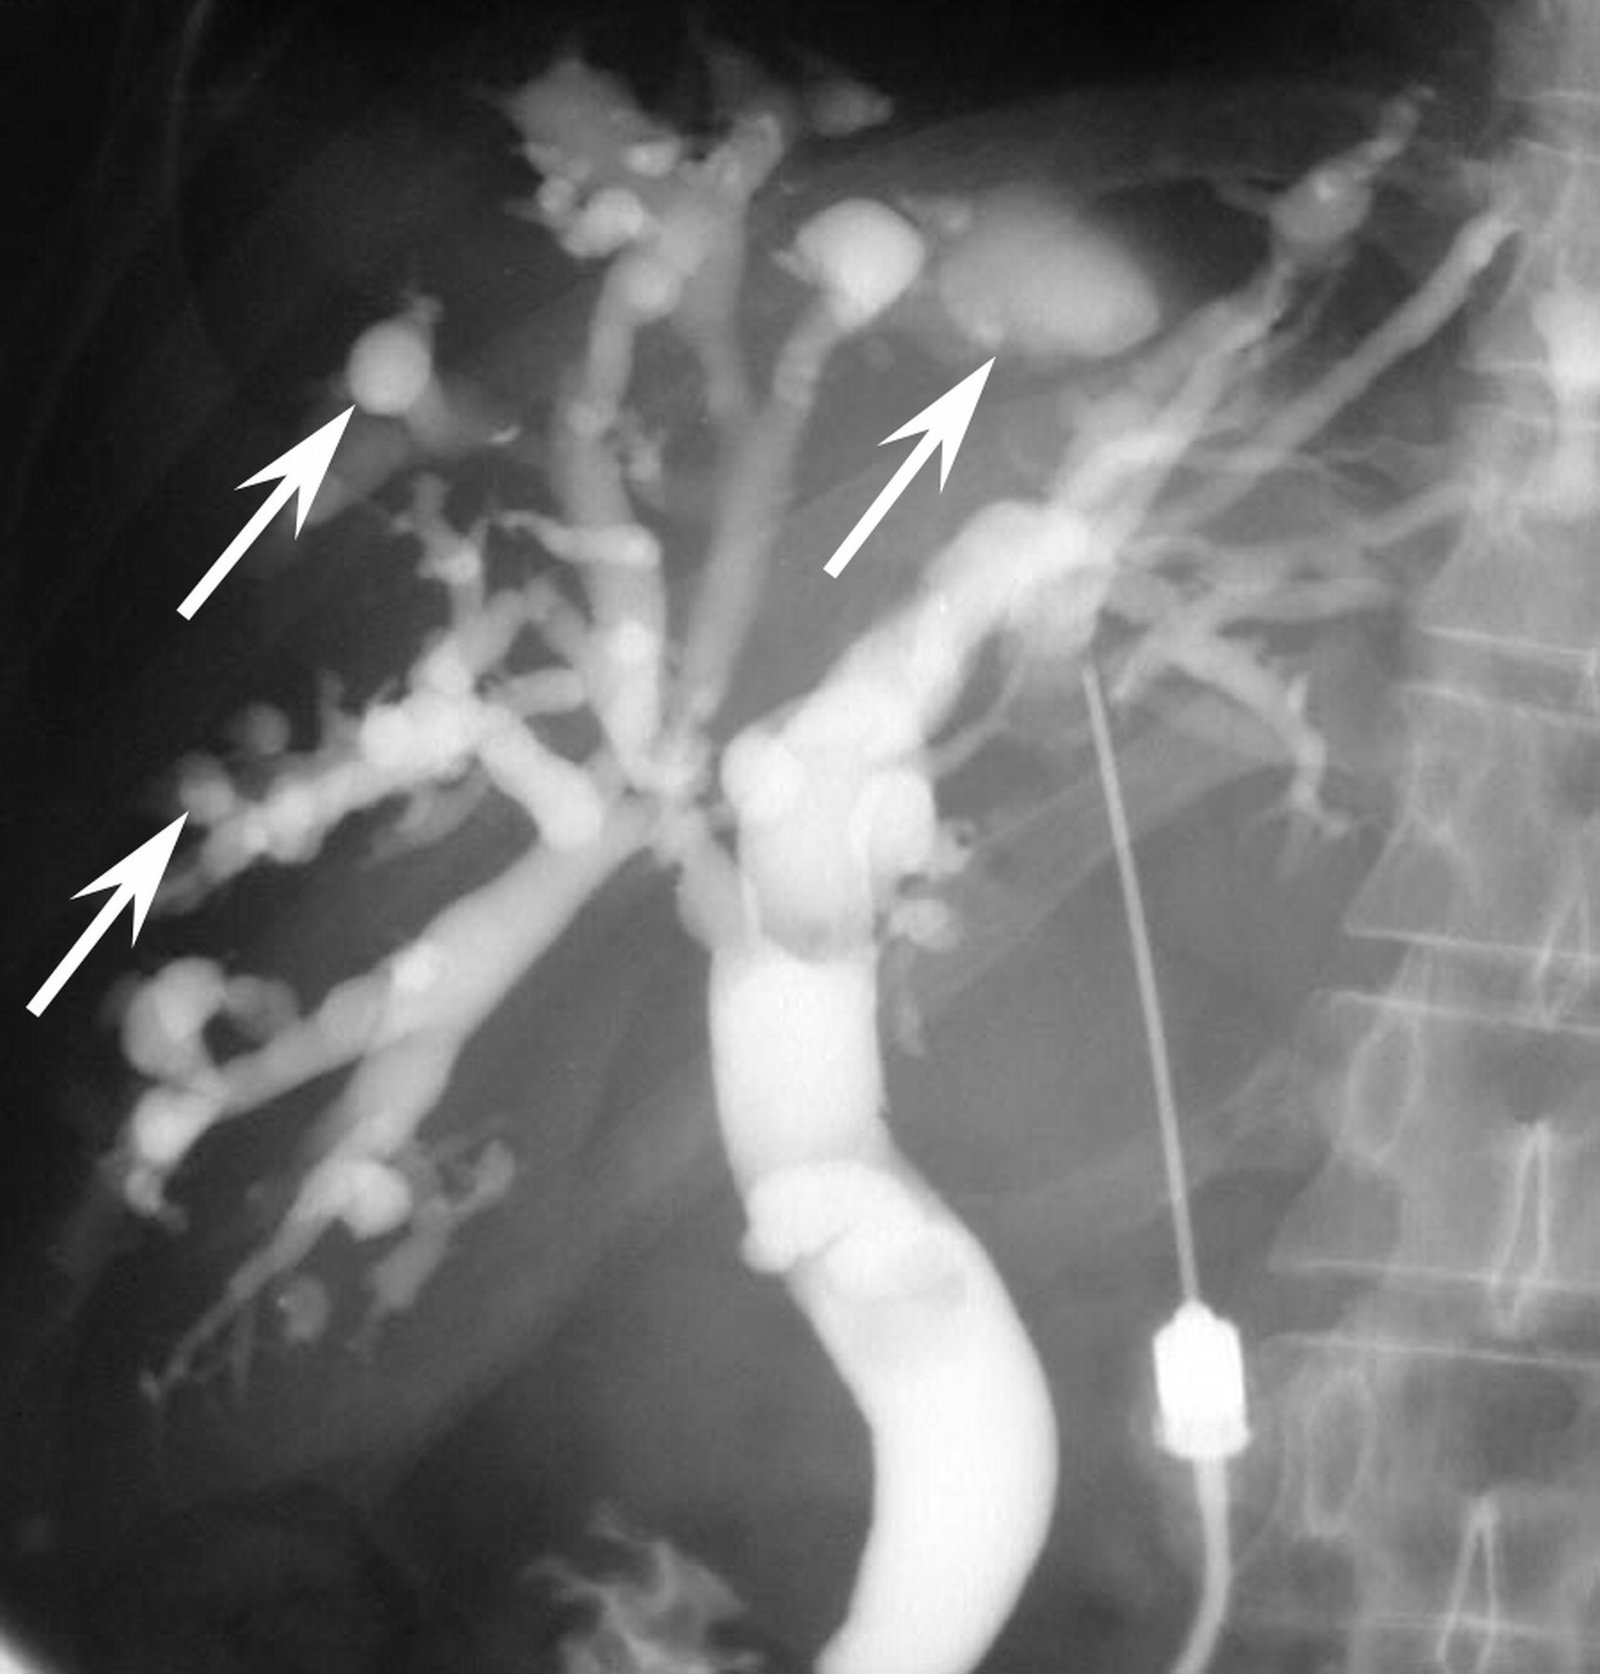

- Diaqnozu dəqiqləşdirmək üçün Qc venaları yoxlanılmalıdır. Bunun üçün dopler USM, KT-angioqrafiya, MRT-angioqrafiyalar və ya kontrastlı venoqrafiya edilir.

PVT diaqnozunu dəqiqləşdirmək üçün portoqrafiya aparılır – Doppler USM, KT və ya MRT angioqrafiya.

Qc venaları yoxlanılmalıdır:

- Doppler USM;

- KT-angioqrafiya;

- MRT-angioqrafiya;

- Kontrastlı venoqrafiya;

Qaraciyər venalarının görünməməsi, kontrastlaşmaması və ya trombla tıxanması.

Portoqrafiya – Doppler USM, KT və ya MRT angioqrafiya;

- portoqrafiyada vena mənfəzində trombun görünməsi;

- venanın distalında genişlənmə və kavernoz transformasiyanın görünməsi;